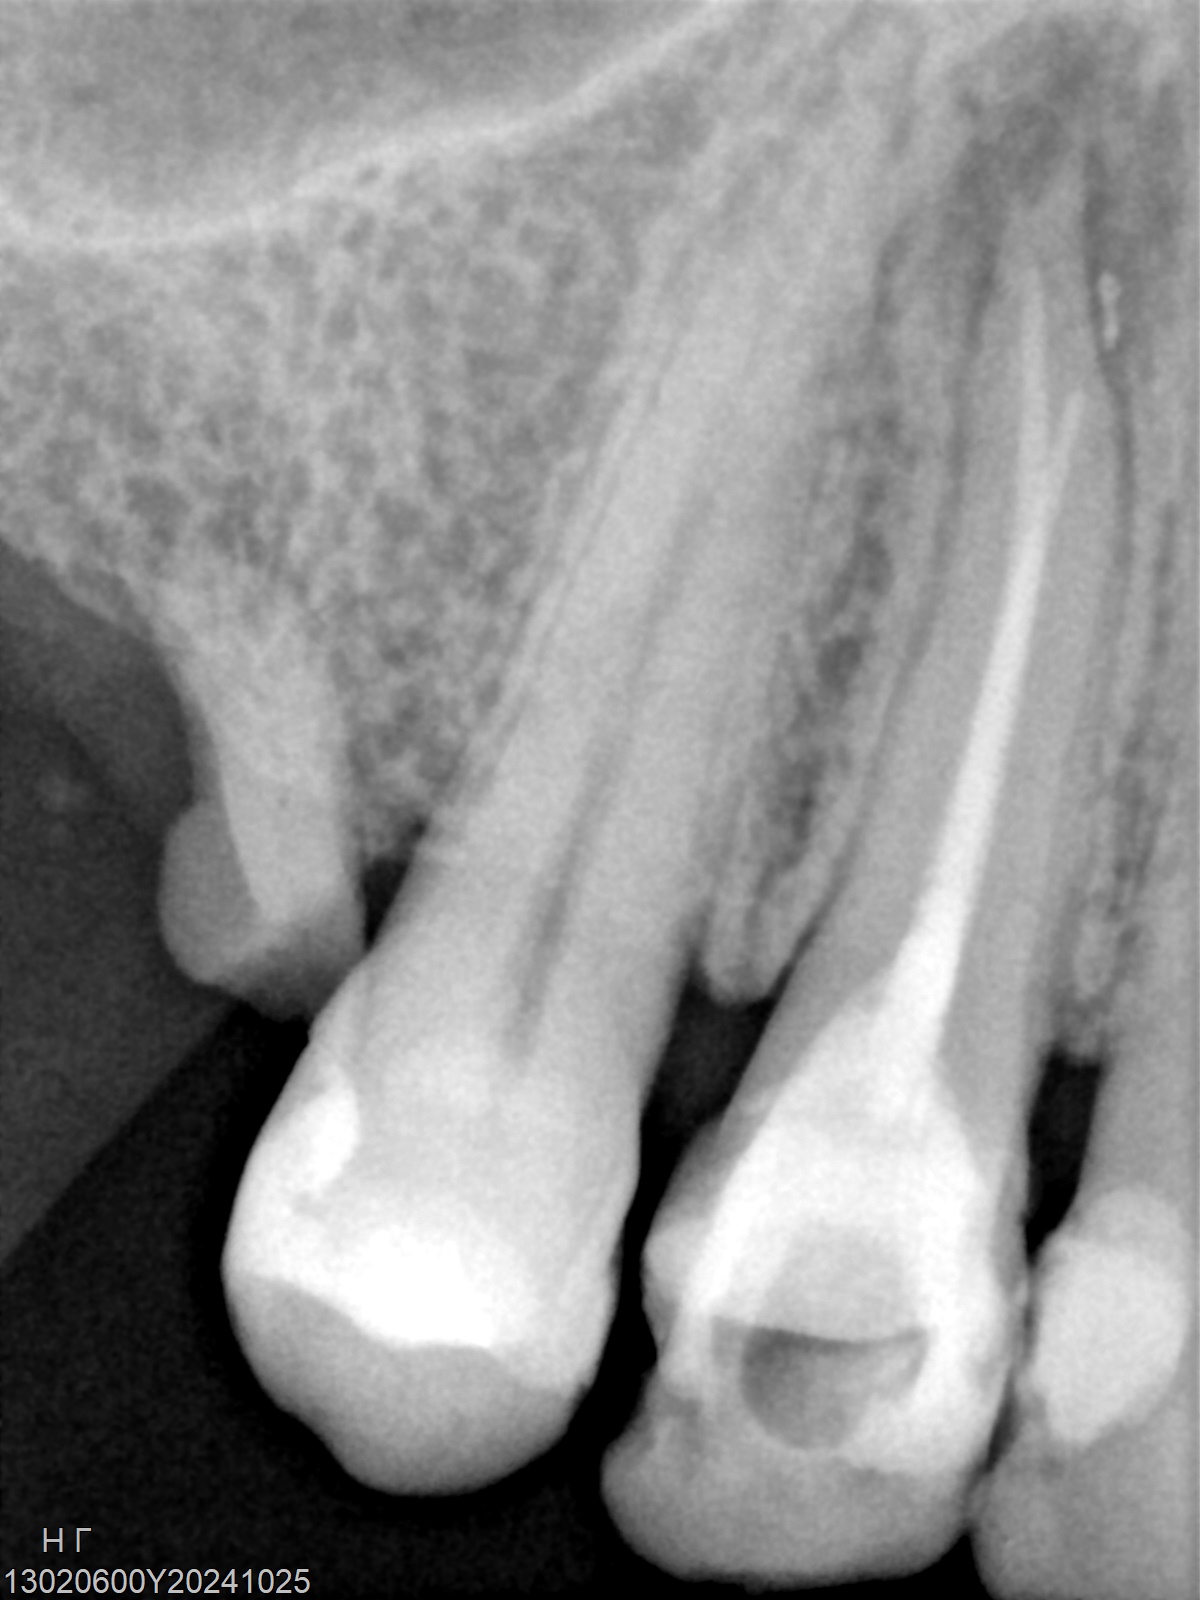

Veja alguns casos de sucesso